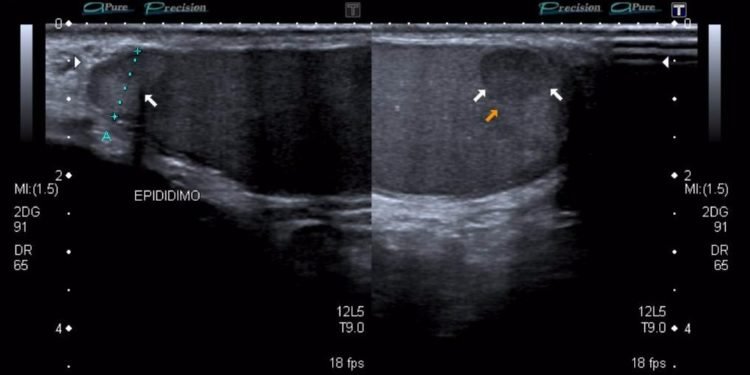

En mayo del 2016, el chequeo semestral mostraba que algo había cambiado: apareció una sombra ovalada hacia el interior del testículo y tenía un diámetro de 6 mm. El ultrasonido no fue concluyente, solo se describía como una estructura hipoecóica de 6 mm de diámetro.

Continué con mis chequeos semestrales y dos años después sabría que la manipulación que se hizo con la biopsia sólo había despertado al monstruo. Las molestias se incrementaron, pero los marcadores tumorales (los análisis de sangre) se mostraban siempre en valores normales: alfafetoproteínas normal, deshidrogenasa láctica normal, gonadotropina coriónica fracción beta normal (los valores de esta última en mujeres es indicador de embarazo, pero en hombres es indicador de cáncer testicular). Todos los análisis de sangre normales, siempre normales y siempre fueron normales incluso hasta los análisis preoperatorios de 3 días antes de la cirugía, pero el ultrasonido no era tan normal, la estructura hipoecóica había ido aumentando de tamaño de 6 a 7 y luego a 9 en octubre del 2017. Mi epidídimo comenzó a aumentar de tamaño, pero es normal, -me decía el urólogo-, debe tratarse de un proceso inflamatorio y me recetaba ceftriaxona para tratar la inflamación como una posible infección de vías urinarias; mientras los análisis de sangre sigan dando normales, no deberíamos de preocuparnos.

11 Julio del 2018: los marcadores tumorales salen normales, pero el ultrasonido indica que el tumor mide 11 mm y está vascularizado. Eso está muy raro, y si mejor ¿ya lo quitamos? -me dice el urólogo-. Mi respuesta: hace 2 años le pedí que me lo quitara y usted me dijo que no, porque era muy joven y aún no tenía hijos. El urólogo me estaba dando tiempo para tener hijos antes de querer quitarme un testículo por un posible tumor testicular. Me programan para estudios preoperatorios y el 31 de julio a las 7pm entro a quirófano donde me practicarían una orquiectomía radical izquierda, es decir, me quitarían el testículo izquierdo.